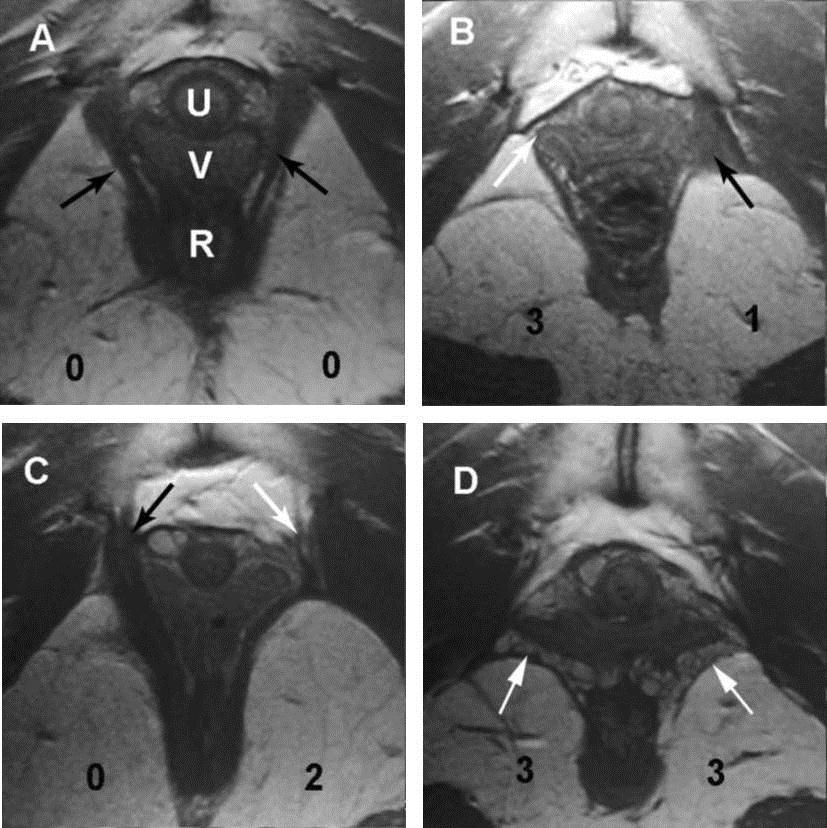

三维/四维盆底超声可以提示盆膈裂孔形态及大小变化,缩肛状态下评估双侧肛提肌有无损伤以及肛门括约肌的完整性,在Valsalva状态下测量盆膈裂孔面积,为盆腔脏器脱垂提供有用的信息,特别是肛提肌的损伤以及盆膈裂孔面积,有文献报道对于盆膈裂孔面积明显增大(>35cm2)且有肛提肌损伤的患者,其术后复发率增高。盆底超声对于产后患者的盆底损伤的预测有很大帮助,能够早期发现潜在压力性尿失禁、肛提肌的损伤以及肛门括约肌的损伤,并能及早告知加强锻炼预防盆底功能障碍性疾病的发生。最近有1例年轻患者,35岁,已顺产两胎,产后2年发现盆腔脏器脱垂,妇科检查时子宫脱出至阴道外,盆底超声检查,右侧肛提肌损伤,盆膈裂孔面积29平方厘米,提示单纯子宫脱垂,无阴道前后壁膨出。此患者如果产后能够超声及早发现盆底损伤,尽早锻炼可能会延缓发病年龄。

MRI图与正常盆底三维图像

双侧提肛肌完整(左图)

双侧提肛肌损伤(右图)